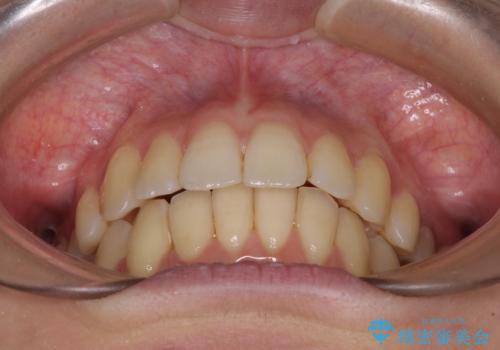

突出した印象のあった前歯をきれいに引っ込めることができたので、口が閉じやすくなり、横顔の印象をスッキリとさせることができました。

でこぼこしていて磨きにくかった歯と歯の間も清掃しやすくなり、患者様には大変満足していただきました。